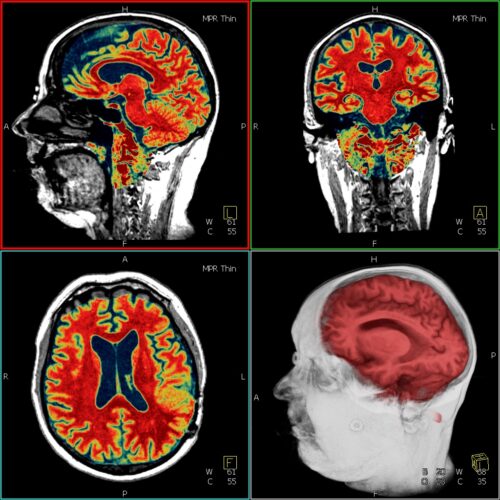

Medizintechnik (

M.Sc.)

"Medizinische Bild- und Datenverarbeitung", "Medizinelektronik", "Medizinische Produktionstechnik, Gerätetechnik und Prothetik", "Health & Medical Data Analytics and Entrepreneurship" oder "Medical Robotics"

Medizintechnik (

B.Sc.)

Studienrichtungen "Medizinelektronik und medizinische Bild- und Datenverarbeitung" oder "Medizinische Gerätetechnik, Produktionstechnik und Prothetik"